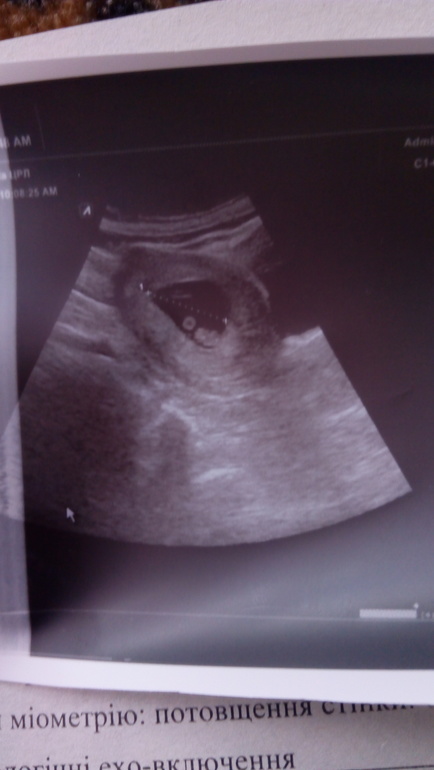

По сроку сегодня 8+1 недель, ктр должен быть 16-17 мм, у меня намеряли 12 мм. ( На срок 7+3 тянет). Пя 37 мм. Жм 4.5.

В заключении Бер 7-8 нед. В остальном все гуд. Да и за рост врач не чего не сказала.

3 числа ( 11 дней назад был ктр 4 мм, пя 17 мм).